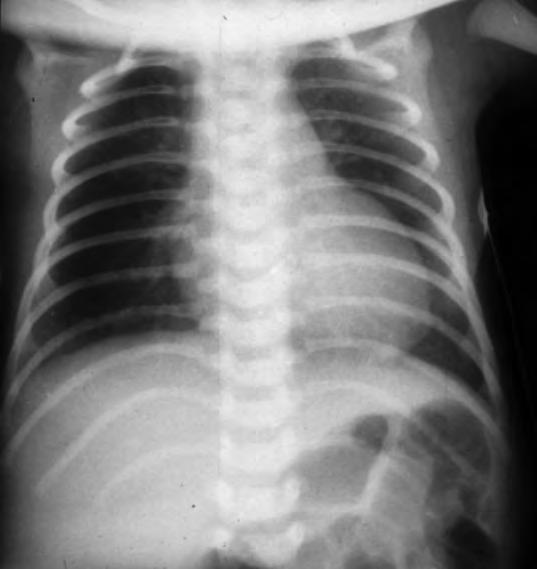

Los síntomas de dificultad respiratoria, taquipnea, retracción sub e intercostal y quejido espiratorio pueden comenzar desde el nacimiento o en las dos primeras horas de vida, alcanzando su máxima gravedad en la mayoría de los casos antes de las 12 horas de vida. Las necesidades de oxígeno suplementario para mantener una oxigenación adecuada son variables, raramente superiores al 40%, y la FiO2 máxima suele alcanzarse antes de las 12 horas de vida. Posteriormente las necesidades de oxígeno empiezan a descender y los signos que indican un aumento del trabajo respiratorio, retracciones, aleteo nasal, quejido, disminuyen su intensidad aunque la taquipnea, con respiración más superficial, persiste entre 24 y 72 horas. Las gasometrías antes de las 6-12 horas de vida pueden mostrar moderada hipoxemia y ligero aumento de la PCO2 con normalización posterior, incluso antes de que los signos clínicos remitan. En la Rx de tórax se pueden observar en diferente grado marcas broncovasculares perihiliares prominentes, condensaciones inhomogéneas difusas, volumen pulmonar adecuado (diafragma a nivel de la 9a costilla) o con ligera hiperinsuflación y, en algunos casos, ligero derrame pleural o líquido en cisuras (Fig. 2.17.1).